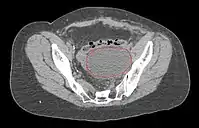

- Postoperative Lymphocele